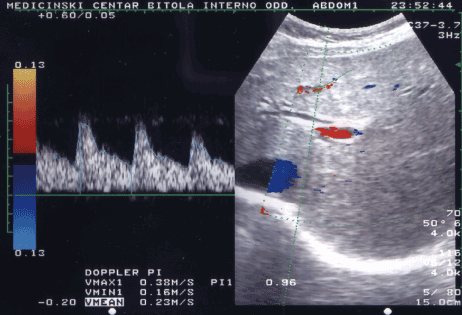

Hepatofugal flow